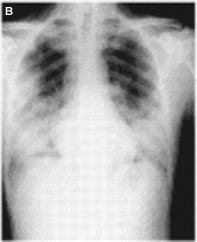

La radiografía (Rx) de tórax puede ser normal durante el pródromo febril (Fig. 2A). Sin embargo, en la fase respiratoria se puede caracterizar por infiltrado intersticial focal que se generaliza, pudiendo encontrarse áreas de consolidación en la fase tardía de SRAS Fig. 2B)(4-6).

Figuras 2A y 2B